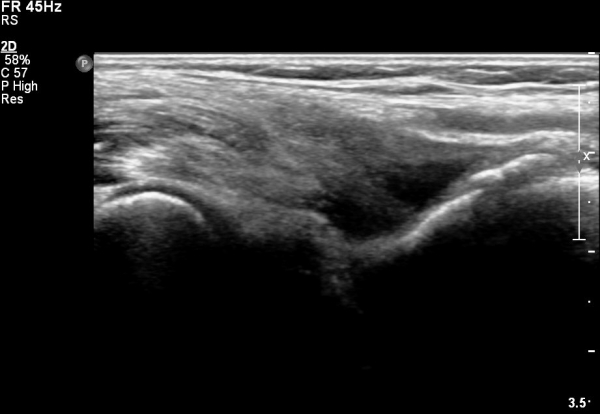

ÆÈ²ÞÄ¡ ¾Õ ÀÌµÎ¹Ú±Ù°Ç È¸´Ü¸ç°Ë»ç¿¡¼­ ÀÌµÎ¹Ú±Ù°Ç ¿ÜÃø¿¡ ¼ö¾×Àú·ù°¡ °üÂûµÊ(»çÁø 1).